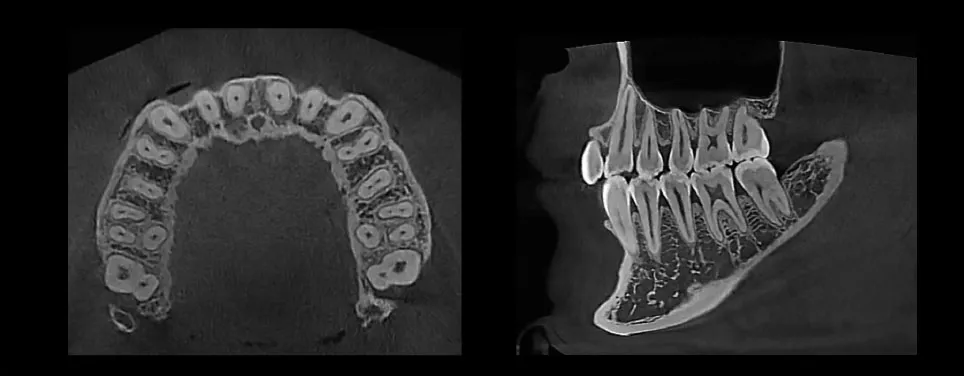

3D Imaging

MAX 18 x 16.5 cm FOV, perfect for capturing dentition, sinus, or TMJ

Expansive FOV (Max 18×16.5cm)

18×16.5 cm FOV allows diagnosis for most maxillofacial structures

Superior Image Quality

Striking contrast and sharpness of images produced by HDX WILL’s image reconstruction technology